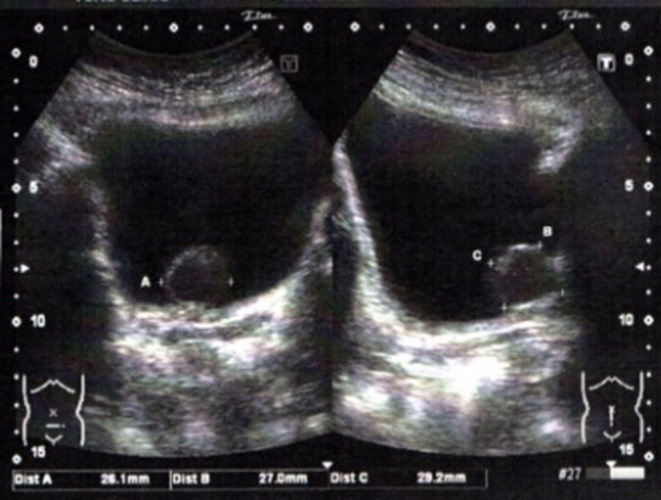

Case presentation: A 53-year-old woman presented to a local clinic with frequent urination and dysuria and was diagnosed with acute cystitis. Her symptoms temporarily improved after taking oral antibiotics, but then flared up repeatedly. Contrast-enhanced computed tomography showed a bladder neck leiomyoma and multiple uterine fibroids. Her body mass index was 27.0 kg/m2. The patient successfully underwent transurethral resection of the tumor. The histopathological diagnosis was bladder leiomyoma.